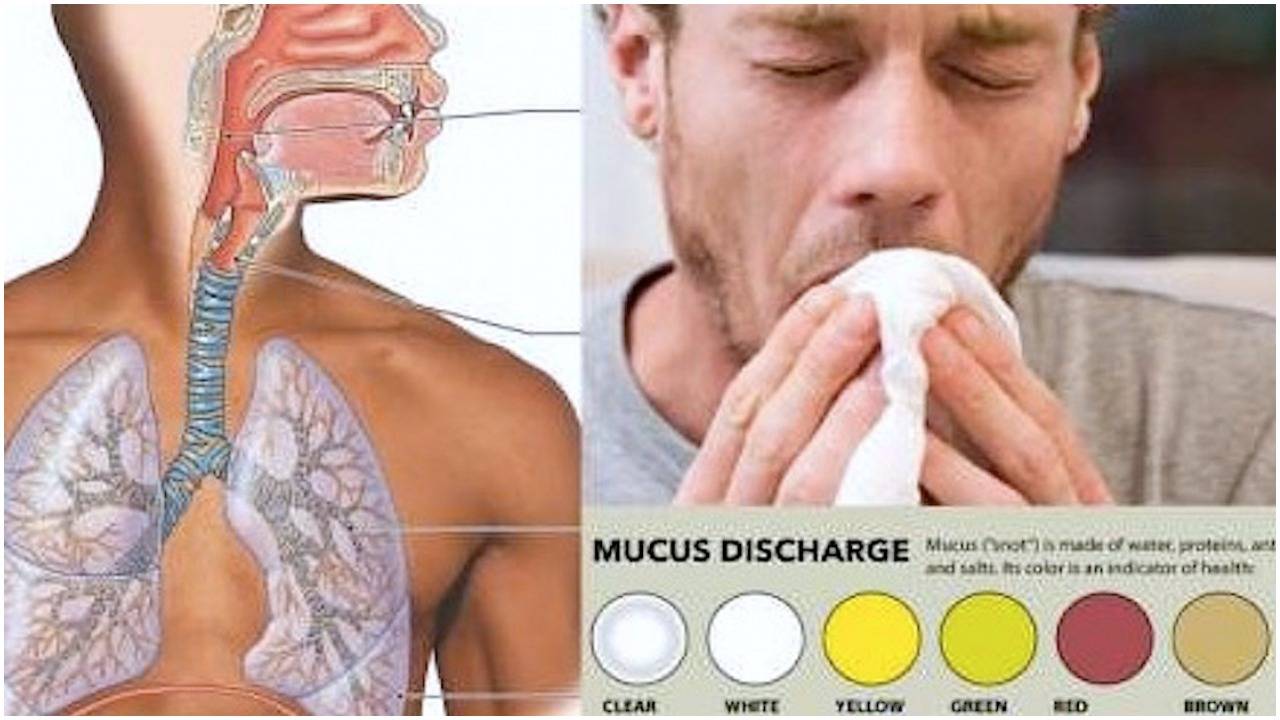

Симптомы и причины скопления воды в легких

Раздел: Ракурсы просвещения